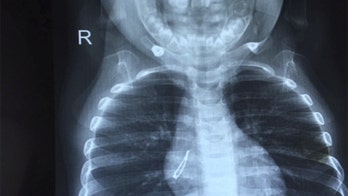

Doctors discover small light bulb inside a child after coughing fit Doctors in India investigating a baby's cough were shocked to find a tiny LED light bulb in her right lung.